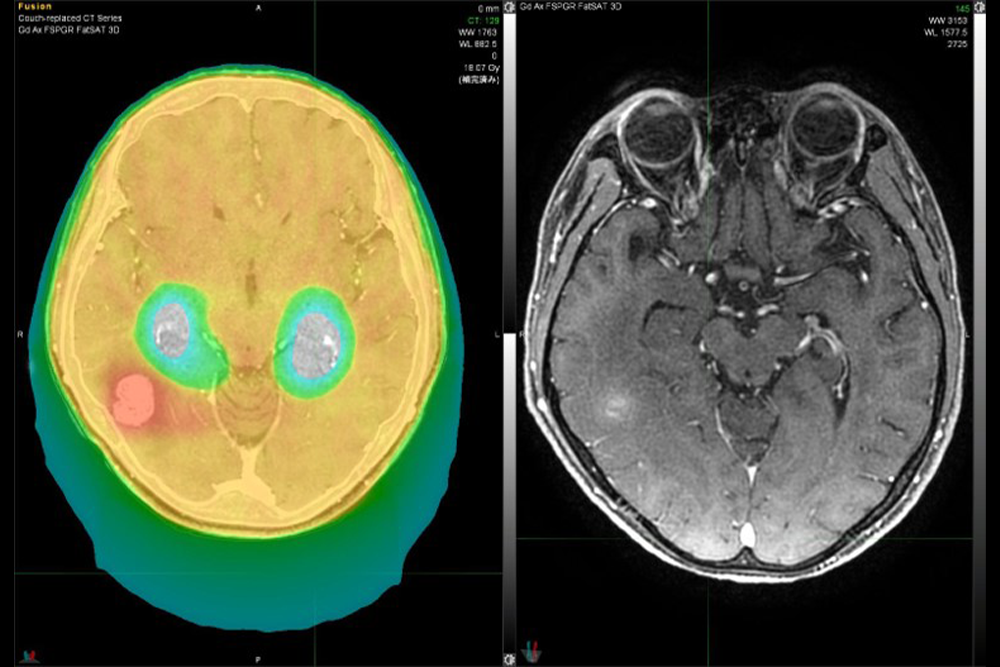

外照射

外照射は体の外から放射線を照射して治療を行う方法です。琉大病院ではTomotherapy、Clinax iXの2台を有し、強度変調放射線治療(IMRT)や定位放射線治療(SRT)などの高精度治療を多数行っています。Tomotherapyに呼吸追尾機能が搭載された装置(Synchrony)が導入されており、呼吸追尾機能を生かした肺や肝臓への定位放射線治療も増加しつつあります。